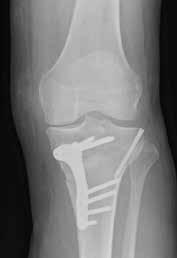

(Top, from left) X-ray images show a normal knee; unicompartment OA with some wearing on inner side of knee; and post-partial knee replacement.

(Bottom, from left)

Tricompartment OA with severe damage to both knees; and post-total knee replacement.

(Right)

Post-knee preservation surgery realigns the knee to take pressure off the damaged portion of the knee joint.

Data show that 80 per cent of patients who underwent a type of preservation surgery known as high tibial osteotomy (HTO) did not need a knee replacement for at least 10 years after the surgery. In HTO, the surgeon creates a wedgeshaped opening in the upper portion of the shin bone via a small 4cm incision. A bone graft wedge is then inserted into the opening and secured in place with a titanium plate and screws to realign the knee and to take pressure off the damaged portion of the knee joint.